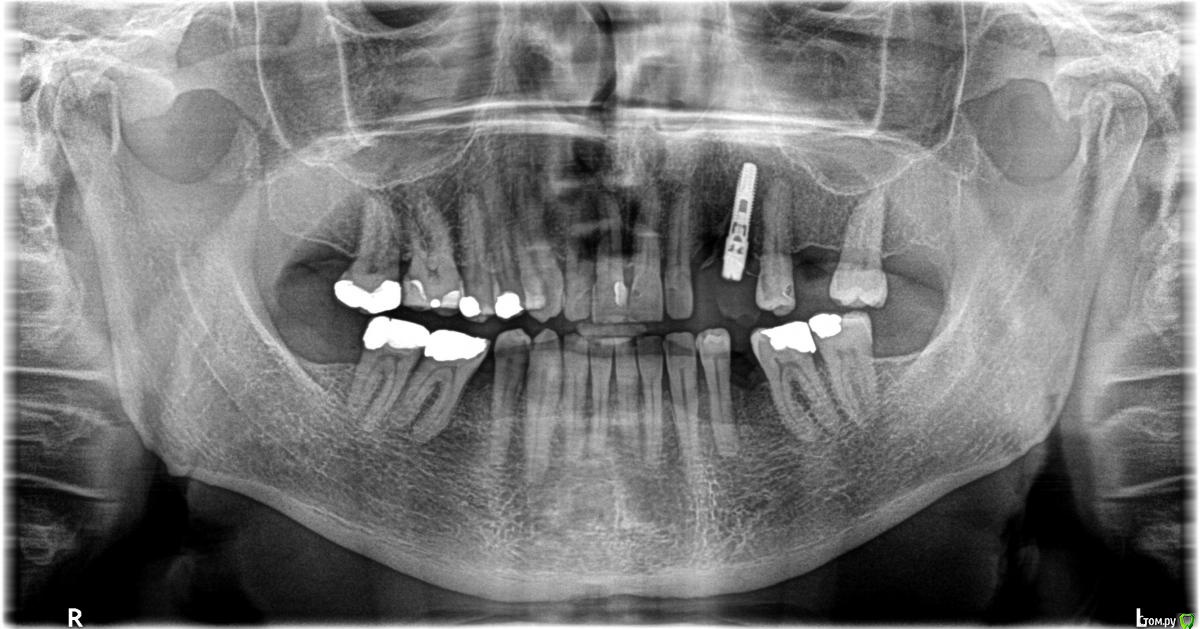

Mark4 Опубликовано 29 августа, 2017 Поделиться Опубликовано 29 августа, 2017 Здравствуйте!2000 году поставили в верхнем рядуна месте отсутствующих слева 3 и 4 зуба имплант /Semados /. Имплант был установлен не совсем перпедикулярно, нохирург сказал, что протезист подкорректирует. Протезист и подкорректировал, поставил один гигантскую коронку / зуб вампира /, но дырку закрыл. Эстетика , честно говоря, меня мало интересовала и все бы ничего, но вскоре пошли проблемы. При нагрузке, надавливании на коронку начинались ноющие болиотдававшиися в голове. И как-то подсознательно я простоперестал есть на левую сторону,поскольку боли могли быть очень сильными, стараясь избегать нагрузки на коронку. Но время шло, правая сторона усиленно изнашивалась и встал вопрос о решении проблемы с болями. С чем могутбыть связаны эти боли? С ошибкой протезирования или имплантации? Стоматологи говорят,что рентген показывает норму, но болит то не рентген. И костная ткань под имплантом тоже рассасывается. Каковы перспективы? http://s018.radikal.ru/i520/1708/79/af09b5c73287.jpg Буду признателен всем ответившим. Ссылка на комментарий

Doctor Vlad Опубликовано 29 августа, 2017 Поделиться Опубликовано 29 августа, 2017 для начала санация рта. на 25 кариозная полость граничит с пульпой зуба. и консультация ортопеда может расфиксация коронки или еще какие проблемы в области импланта Ссылка на комментарий

Doctor Vlad Опубликовано 30 августа, 2017 Поделиться Опубликовано 30 августа, 2017 Признателен всем откликнувшимся, но к доктору Владу вопрос - 25 - это следующий зуб после импланта и коронки?да! это следующий за имплантом зуб. на рентгенснимке он ближе всего к импланту Ссылка на комментарий